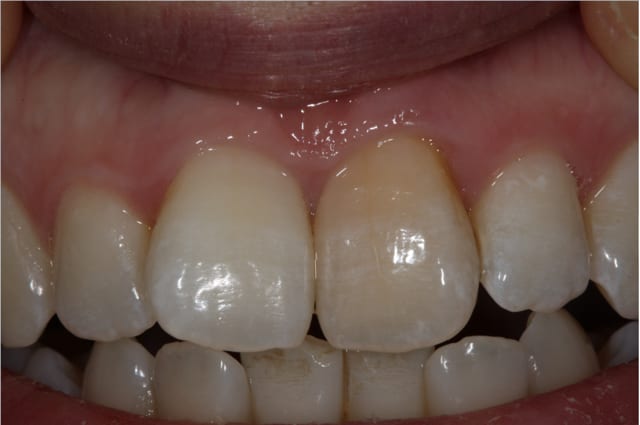

PS/ Je prolonge le ttt jusqu'à la semaine prochaine en espérant gagner encore un poil sur l'opacité .

Le protocole est le même que pour une dent dépulpée ; isolation en regard présumé du canal , un peu plus parce que j'ai cherché un moment en plusieurs séances . Perborate , et voilà .

3 séances à 7 jours d'intervalles .

Si on décide d'être le moins invasif , j'ai jugé raisonnable de tenter quand même malgré l'impossibilité de repérage de l'entrée du canal . Faire une facette c'est passer un cap , et je n'ai de prothésiste capable de reproduire les stries visibles sur la photo de départ de tout façon donc je n'ai compté que sur moi même .